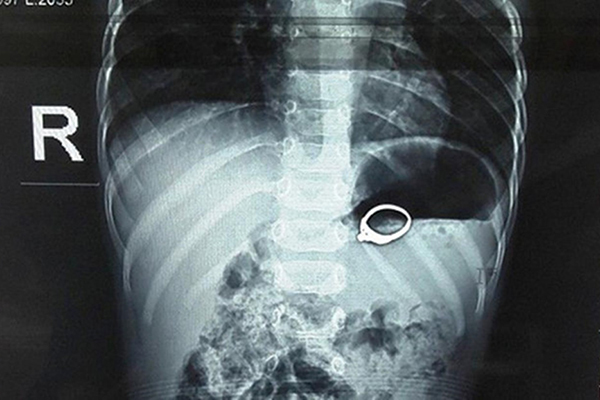

Bé trai 13 tháng tuổi ở Nghệ An nuốt nhẫn đính đá vào bụng

Một bé trai ở Nghệ An vô tình nuốt chiếc nhẫn đính đá vào bụng, gây xước niêm mạc, xung huyết dạ dày.